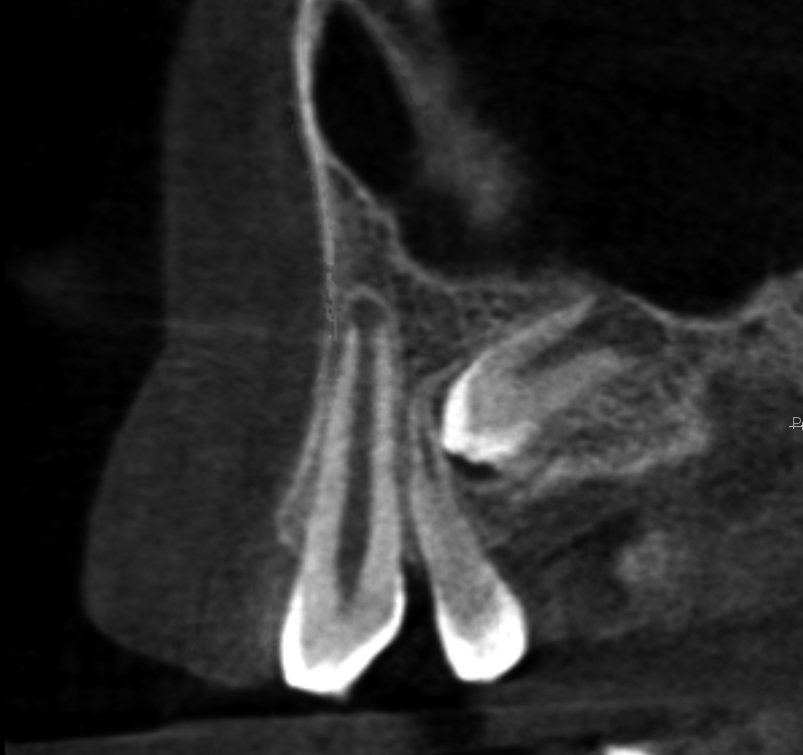

Resorpcja zęba to proces powstania ubytku twardych struktur zęba wywołanego przez osteoklasty bez kontaktu ze środowiskiem jamy ustnej, między innymi na skutek ucisku wywieranego przez ząb zatrzymany. Dla lekarza ortodonty jest istotne ustalenie, czy zęby zatrzymane lub twory nadliczbowe powodują resorpcję zębów stojących w łuku w celu wczesnej eliminacji przyczyny resorpcji. Celem pracy jest przedstawienie opisu przypadku zastosowania tomografii stożkowej w diagnostyce nieprawidłowo położonych zawiązków zębów przedtrzonowych drugich górnych. Stwierdzono, że tomografia stożkowa jest skuteczną metodą oceny wczesnej resorpcji zewnętrznej korzeni zębów.

Tooth resorption is the process of appearing of a defect of hard tissues of teeth caused by osteoclasts not having contact with oral cavity environment, eg. due to mechanical pressure exerted by an impacted tooth. It is essential for an orthodontist whether impacted teeth or supplementary teeth cause resorption of erupted teeth in order to early eliminate the causative factor of the resorption. The aim of the paper is to describe a case report of cone-beam computed tomography (CBCT) in diagnostics of incorrectly located germs of upper second premolars. It was found that CBCT was an efficient method of imaging of early external root resorption.